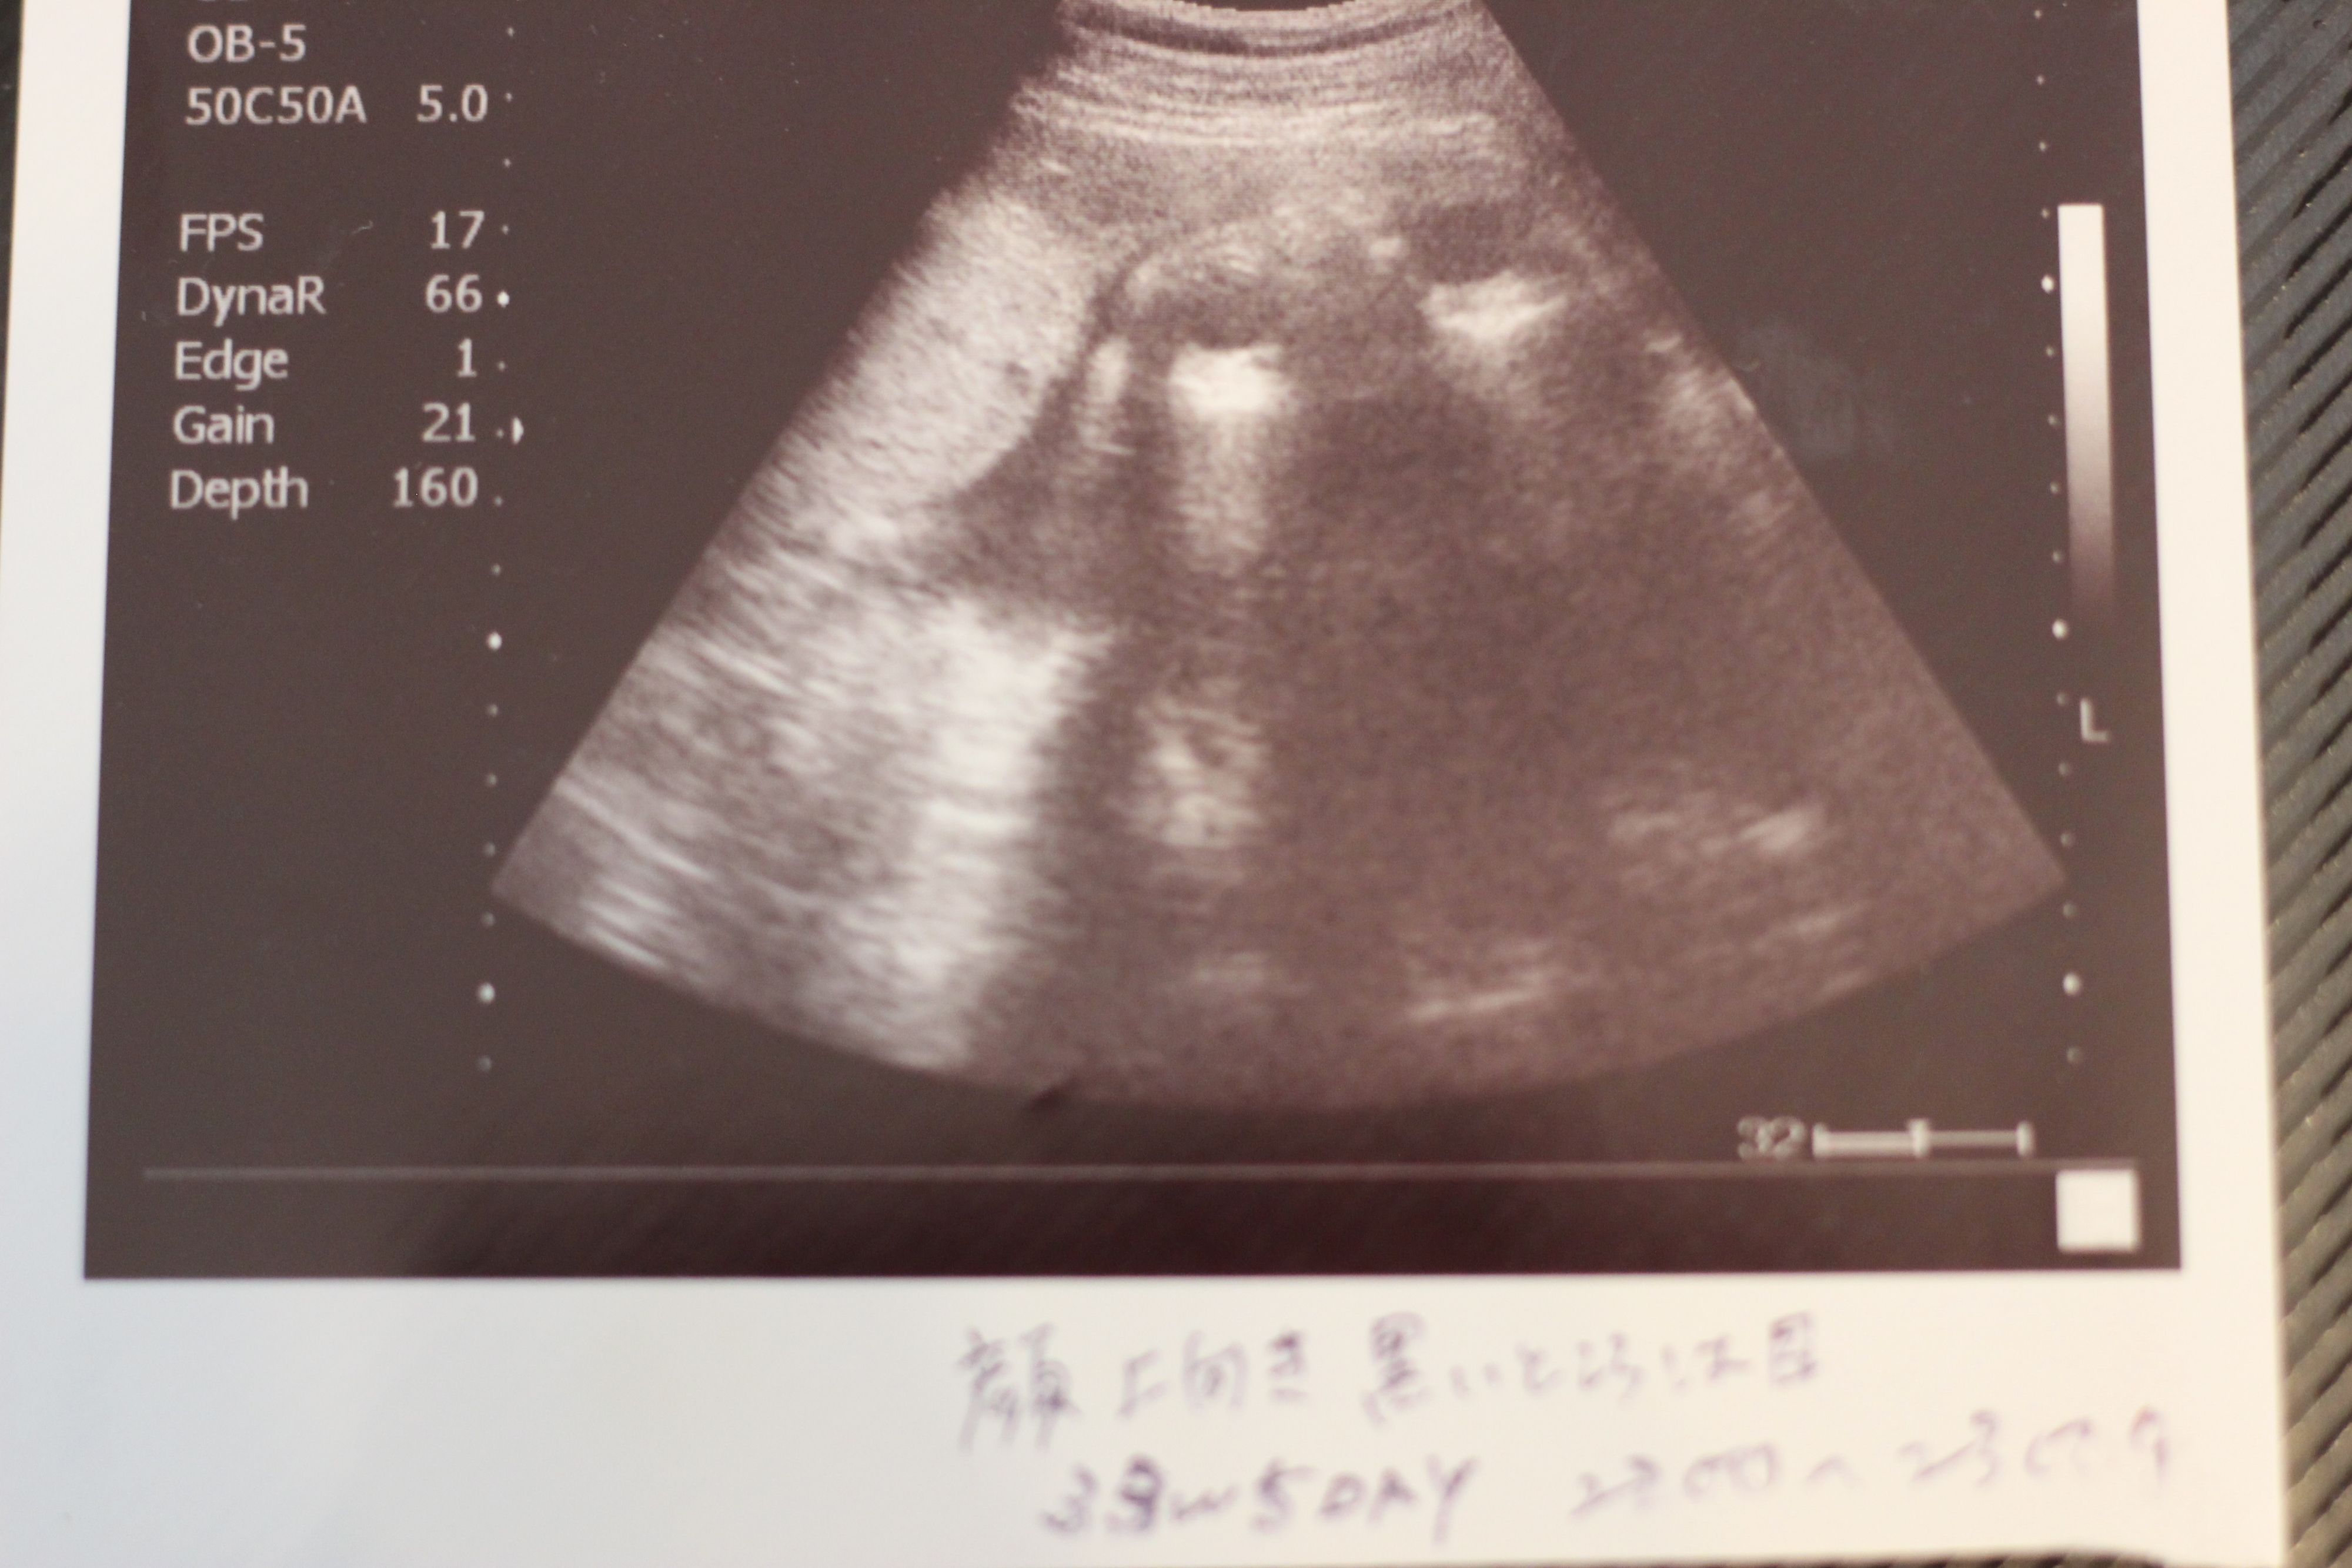

妊娠32週目のエコー写真

妊娠32週目。赤ちゃんの体重1915g。この頃の楽しみは医師軍団による回診で、ドラマ「白い巨塔」の再現VTRを見ているようでした。実家の母に頼んでウエストサイズ100cmのパジャマを作って送ってもらいました。